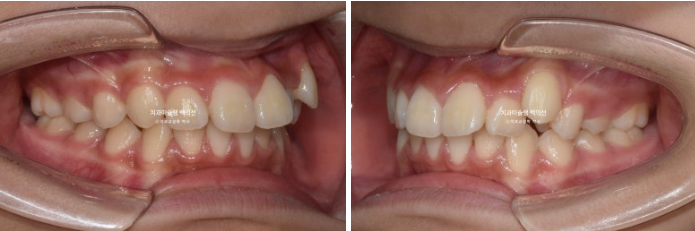

상악만 발치교정 결과 교합은 이러합니다.

총 치료기간은 2년 3개월입니다.

23.02~25.05

뻗치치도 옥니처럼 뒤로 너무 들어가지도 않은 적절한 앞니 각도

입술 돌출 역시 과하지 않게 입술 볼륨감을 유지한채 적당히 들어갔습니다.

결과에서 보듯 작은어금니 4개 발치는 불필요했습니다.

윗니돌출이 해소가 되면서 입술이 편하게 다물립니다.

치료당시 아직 중학생이라 성장에 의해 아래턱이 조금 성장했습니다.